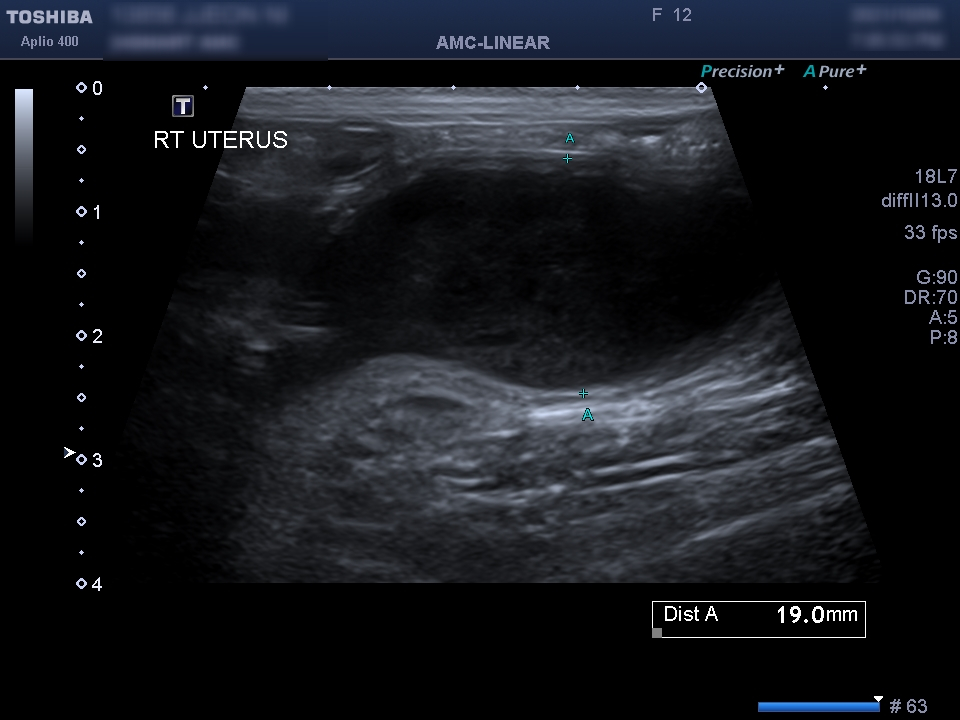

동물 병원에 내원해 주시고, 수의사의 판단으로 검사를 통해 확인이 됩니다.기본적으로 필요한 최소한의 검사는 복부 초음파 검사나 X 선 검사, 혈액 검사 등이 진단에 필요합니다.

신체 검사 결과 생식기 쪽에서 삼출물이 확인되었습니다.자궁 축농이 의심되는 상황이어서 초음파 검사를 통해 확진을 할 수 있었습니다.

초음파 검사를 통해 확장되어 있던 양쪽 자궁을 확인할 수 있었습니다